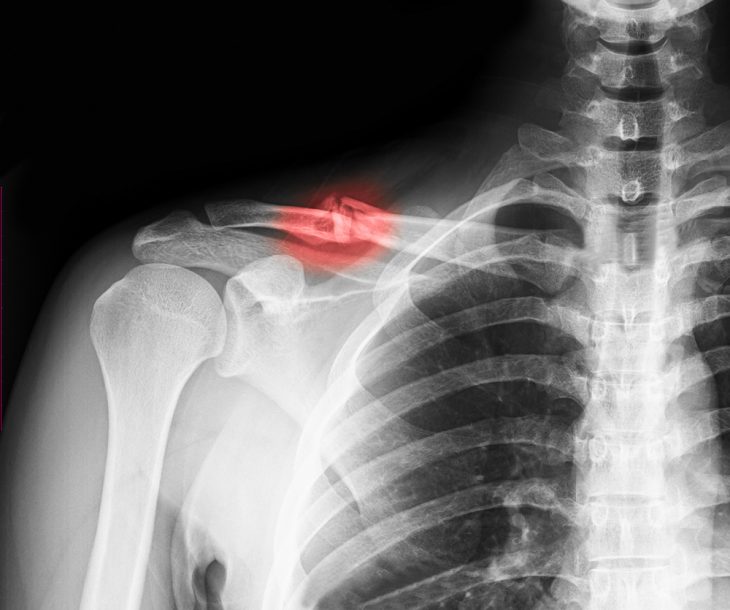

При появлении подозрений на перелом ключицы необходима консультация ортопеда. После осмотра доктор назначит выполнение рентгеновских снимков в двух проекциях, которые позволят получить детальные данные о состоянии отломков ключицы и выявить возможные осложнения (разрывы нервов, сосудов, купола плевры).

Диагностика

В большинстве случаев перелом ключицы выявляется уже при осмотре пострадавшего врачом. Для подтверждения диагноза и уточнения характера перелома (наличия смещений, повреждений купола плевры, сосудов и нервов) всегда выполняется рентгенологическое исследование. Снимки проводятся в двух проекциях: прямой и боковой.

Переломы ключицы наблюдаются часто и сопровождаются болью, изменением формы ключицы, отеком и нарушениями в движениях руки. Они выявляются при осмотре врачом и на рентгеновских снимках. Для лечения таких травм могут использоваться консервативные и хирургические методики. При отсутствии смещения выполняется иммобилизация плечевого пояса до срастания кости, а при наличии смещений для сопоставления отломков выполняется открытая или закрытая репозиция.